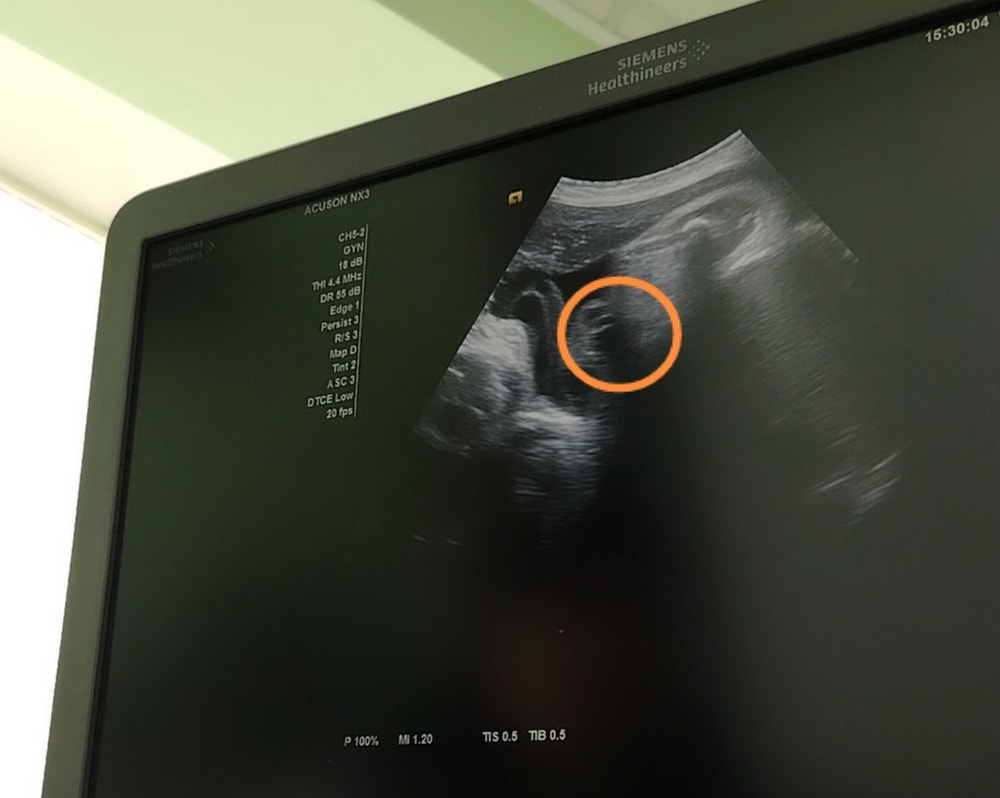

Затрудняюсь с категориейДевочки как думаете, у девочки могут так свисать из ягодиц половые губы🤔? На втором скрининге, на современном аппарате сказали 100% девочка, в 33 и 37 недель сказали что больше теперь на кукушата похожи, пол плохо видно, ещё пуповиной всё перекрыто. Как на Ваш взгляд девочка или мальчик?

Эльза, а на этом стоп кадре вроде как писюн вверх к мочевому задран, или это такие половые губы🤔?